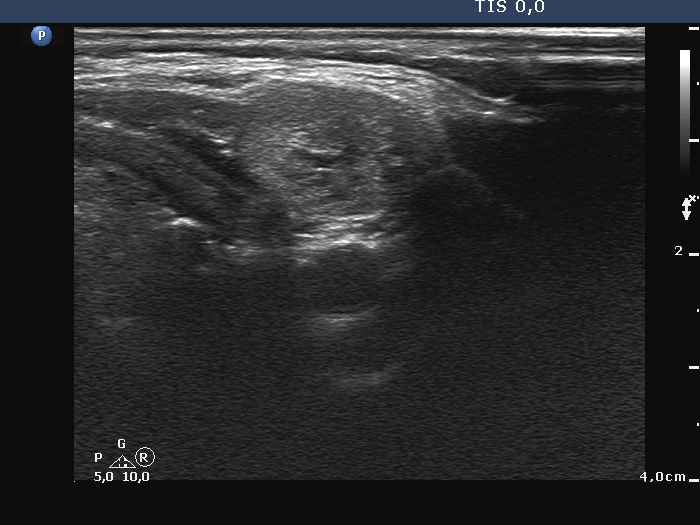

Ultrasonography. There was no thyroid tissue in the thyroid beds. Approximately 7 cm above the thyroid in the left side of the neck there were multiple, moderately hypoechoic lesions which presented tiny cystic areas. They had vascularity but did not have capsule.